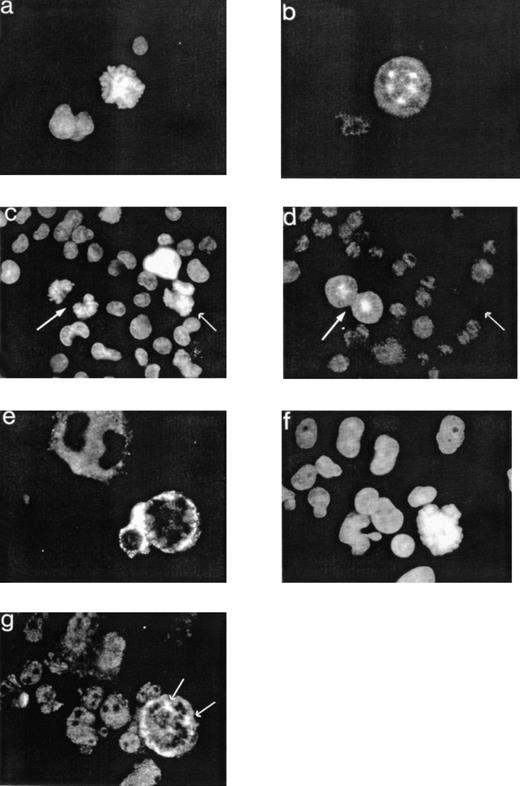

To further examine the localization of cyclin B1 during endomitosis, standard immunofluorescence analysis with the anti-cyclin B1 MoAb and Hoechst dye was performed. In endomitotic MKs, faint cyclin B1 staining delineated the mitotic spindle (Fig 5a and b). In some MKs at late stages of the endomitosis (anaphase), no cyclin B1 was detected, suggesting a degradation of the protein by the proteasome (Fig 5c and d). To clearly demonstrate that these polyploid cells correspond to true MKs, a triple staining was performed (anti-cyclin B1, Hoechst, and vWF) that confirms the results given above (Fig 5e, f, and g). To further characterize the cyclin B1 and CDK1 in MKs, polyploid MKs were purified. Cultured MKs (day 9) were labeled with an anti-CD41b MoAb (anti-GpIIb) and the 33342 Hoechst dye. CD41+ MKs were sorted using a 200- or 300-μm nozzle according to their ploidy into two cell fractions (2N/4N and >4N cells). Cell aggregates were excluded using the pulse processors of the cytometer. This approach allowed us to obtain a relatively pure population of MKs (>95%) with a purity of greater than 90% of the different ploidy classes. However, the more rare 8N MKs were contaminated by MK aggregates, which represented on average 5% of the cells as determined by microscopic examination. Such a cell sorting is shown in Fig 6a and b. Reanalysis of the sorted fractions confirmed these microscopic examinations (Fig 6c, d, and e). The presence of cyclin B1 and CDK1 proteins was determined by Western blot analysis on cell lysates from purified MKs. As shown in Fig 7a, the 62-kD cyclin B1 was detected in both MK fractions. The analysis was performed on the same number of cells for both MK fractions; the higher expression of cyclin B1 in the >4N MKs than in the 2N/4N cells could be the reflect of higher amounts of protein per polyploid MK. When the lanes were loaded with an equal quantity of proteins from 2N/4N and polyploid MKs, the same amounts of cyclin B1 were present in both MK fractions (Fig 7b). Cyclin B1 was detected with the same apparent molecular weight as in the controls (UT-7 c-mpl cell line). In addition, a faint band with a lower molecular weight (57 kD) was sometimes observed in MK samples, with marked differences in intensity among experiments. This band may correspond to the heavy chain of the Ig that was used for MK purification. CDK1 was also detected on immunoblots in both cell fractions and was expressed at a high level in 2N/4N MKs and polyploid MKs (Fig 7c and d). Two molecular forms could be visualized as in control cell lines (UT7-c-mpl, U937, and HL60). The lower molecular form corresponding to dephosphorylated CDK1 was predominent in both MK fractions.

Localization of cyclin B1 in endomitotic MKs. Cultures were performed as described in Fig 1 and cells were stained as described in Fig 3 by an anti-cyclin B1 polyclonal antibody (b and d; TRITC), an anti-vWF MoAb (e; FITC), and the Hoechst dye (a and c). They were examined by conventional fluorescent microscopy (original magnification × 500). In this polyploid MK in endomitosis (a), cyclin B1 staining draws the mitotic spindle with its multiple asters. In two MKs in metaphase, cyclin B1 is detectable (arrows on the left; c and d). In contrast, in a polyploid MK with an anaphase figure (arrow on the right; c and d) as shown by segregation of the chromatids, cyclin B1 is undetectable. In this endomitotic MK (f) expressing the vWF (e), cyclin B1 colocalized with the asters, as shown by the arrows.